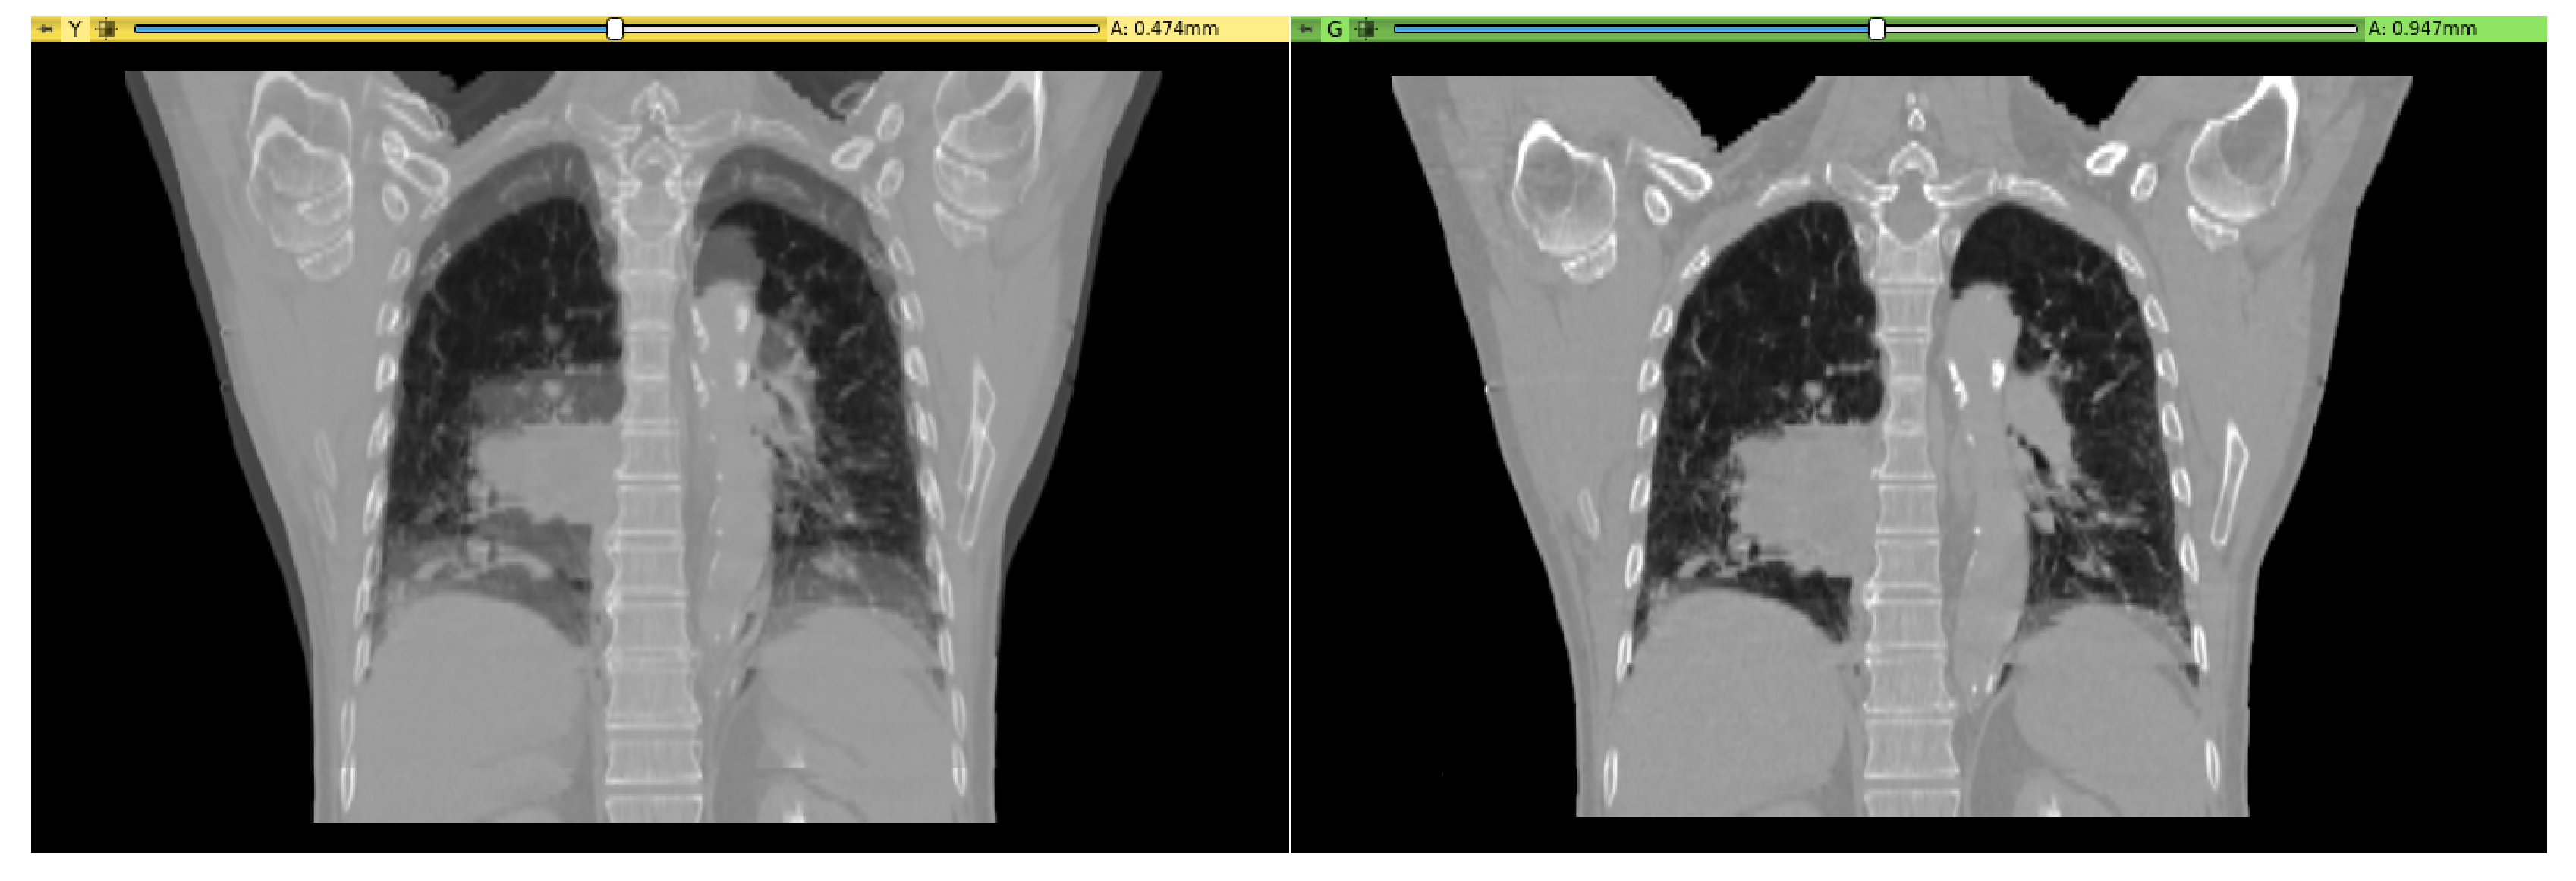

2.3. Exemplary Use Cases

2.3.1. From External Environment to Medical Imaging Platform

2.3.2. From Medical Imaging Platform to External Environment